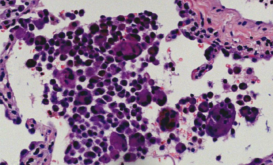

外科肺活检,肺组织病理提示巨细胞性间质性肺炎(GIP)。

ero为什么不显示叶俏教授:HRCT是发现和鉴别「过敏性肺炎」的重要环节,何种表现指向预后不良?使患者发病的危害因素躲在哪些环境中?_https://www.jmylbn.com_新闻资讯_第49张

对于过敏性肺炎,我们除了做临床和肺功能的评估,还需要做支气管镜,支气管镜下可以看到淋巴细胞的数量和百分比都显著增加,箭头处可见激活的淋巴细胞胞浆丰富,核呈分叶状。[35]

ero为什么不显示叶俏教授:HRCT是发现和鉴别「过敏性肺炎」的重要环节,何种表现指向预后不良?使患者发病的危害因素躲在哪些环境中?_https://www.jmylbn.com_新闻资讯_第58张

肺组织病理中,非纤维化型HP包括细胞性间质性肺炎(可见细支气管中心性分布,细胞性NSIP型,以淋巴细胞为著)、细胞性细支气管炎、未形成非坏死性肉芽肿(与结节病的肉芽肿呈显著差别)。纤维化型HP包括慢性纤维化性间质性肺炎(结构扭曲、成纤维细胞灶±胸膜下蜂窝肺纤维化性NSIP型)、气道中心性纤维化。

比如细胞性细支气管炎(下图左),可以看到很多淋巴细胞浸润;还有非坏死性肉芽肿炎(下图中),肉芽肿的边界并不清楚,有一些内上皮细胞和炎症浸润;细胞性慢性间质性肺炎——「NSIP样改变」(下图右)。